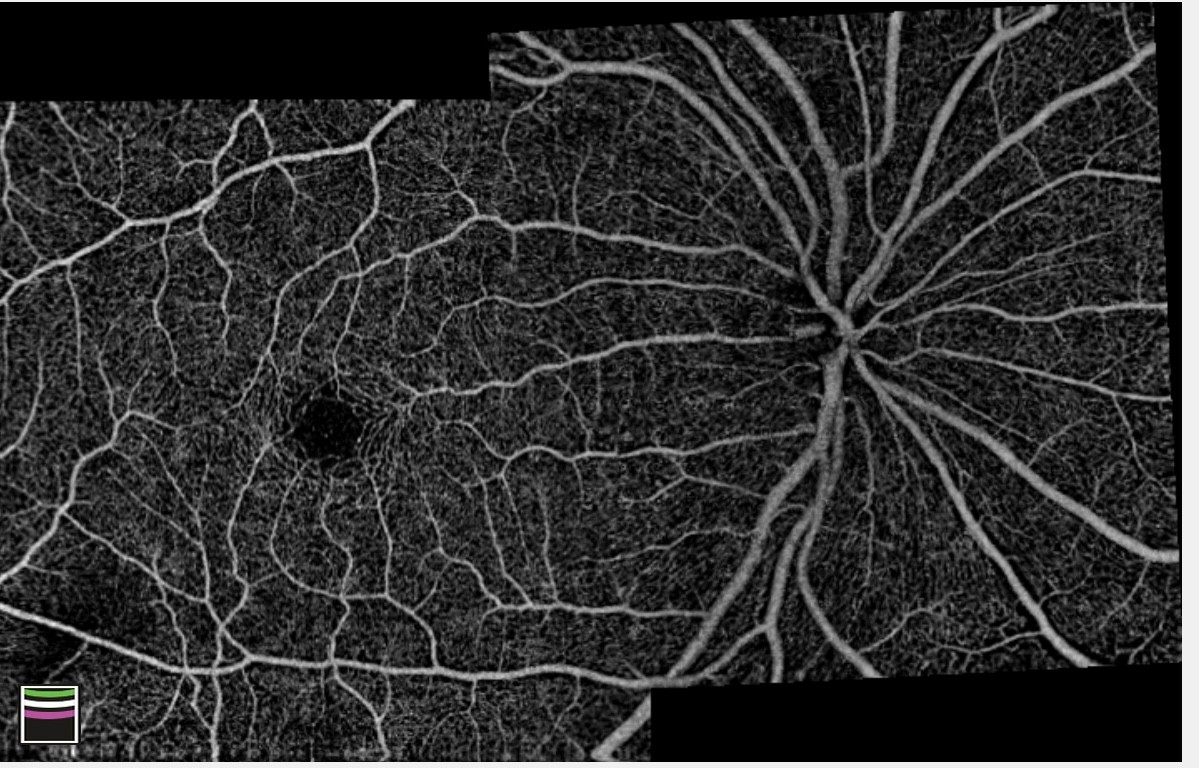

La evaluación de la circulación en el polo posterior del globo ocular es crítica en la valoración clínica de los pacientes.

La OCT-A, es una nueva tecnología que permite hacer angiografía de coroides, retina y nervio óptico basada en tecnología de OCT. La OCT-A permite detectar el flujo vascular no solo en los grandes vasos de la coroides y de la retina, sino también en los capilares. Con esta tecnología no es necesaria la inyección de medios de contraste en la circulación del paciente para la adquisición de imágenes, lográndose imágenes de angiografía de alta resolución y en 3D.

Esta nueva técnica requiere de un cuidadoso estudio y comparación con la AGF, que es el método que hasta el momento provee más información.